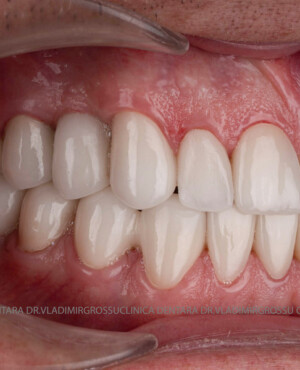

Protezarea pe implanturi dentare este soluția modernă, estetică și funcțională pentru înlocuirea dinților lipsă. Această procedură combină precizia chirurgicală cu tehnologia avansată de laborator pentru a reda pacienților zâmbetul natural, vorbirea clară și capacitatea de a mânca fără restricții.

- Estetică superioară – imită perfect dinții naturali

- Coroane din zirconiu sau ceramică integrală

- Materiale premium – zirconiu, ceramică E-max, titan pur